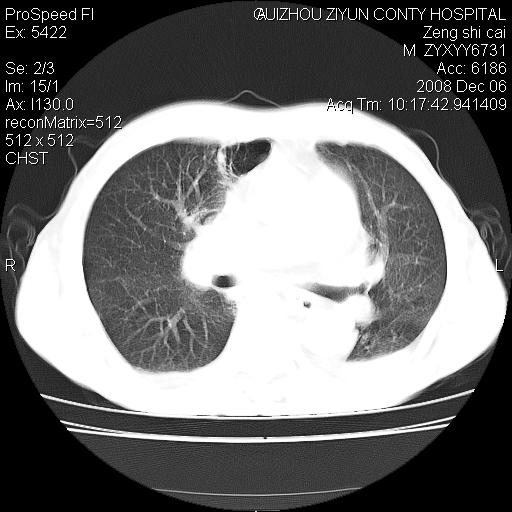

标题: CT16961:M、71岁,咳嗽半年,无血痰;胸片示右肺占位。 [打印本页]

标题: CT16961:M、71岁,咳嗽半年,无血痰;胸片示右肺占位。

右肺癌并纵隔淋巴结及胸膜转移可能性大

右肺癌并纵隔淋巴结及胸膜转移。建议气管镜

右肺纵隔型肺癌伴纵隔淋巴结及胸膜转移!

右肺纵隔型肺癌伴纵隔淋巴结转移!双侧胸水!

1)考虑右肺上叶纵隔型肺癌伴纵隔淋巴结转移。2)心包积液,双侧胸腔积液。

右肺癌并纵隔淋巴转移,腹膜后转移可能性大,两侧胸腔积液

右肺上叶纵隔型肺癌伴纵隔淋巴结转移。心包积液,双侧胸腔积液。

右上肺癌并纵隔淋巴结及胸膜转移。

右肺纵隔型肺癌伴纵隔淋巴结转移!双侧胸水\\心包积液

右肺纵隔型肺癌伴纵隔淋巴结及胸膜转移